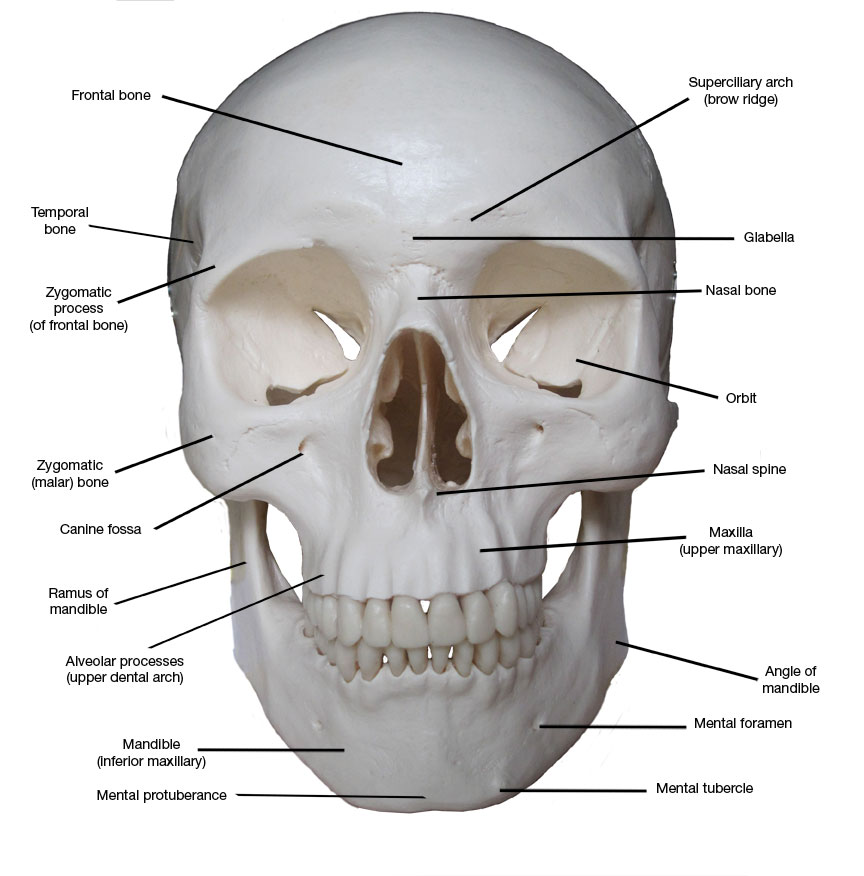

Prepare to be captivated by List, a showcase of real human skull front view black and white imagery powered by ieltschampions.edu.vn. More related visuals are below.

real human skull front view black and white

Posts: real human skull front view black and white